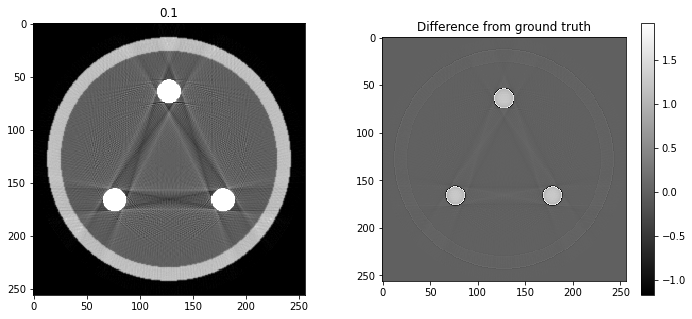

# Question 12

search = np.linspace(0,1,11)

for alpha in search:

rec = out+alpha*reproj

f,ax = plt.subplots(1,2,figsize=(12,5))

ax[0].imshow(rec,vmin=0,vmax=0.5)

ax[0].set_title(alpha)

im = ax[1].imshow(img[80]-rec)

f.colorbar(im,ax=ax[1])

ax[1].set_title('Difference from ground truth')

plt.show()